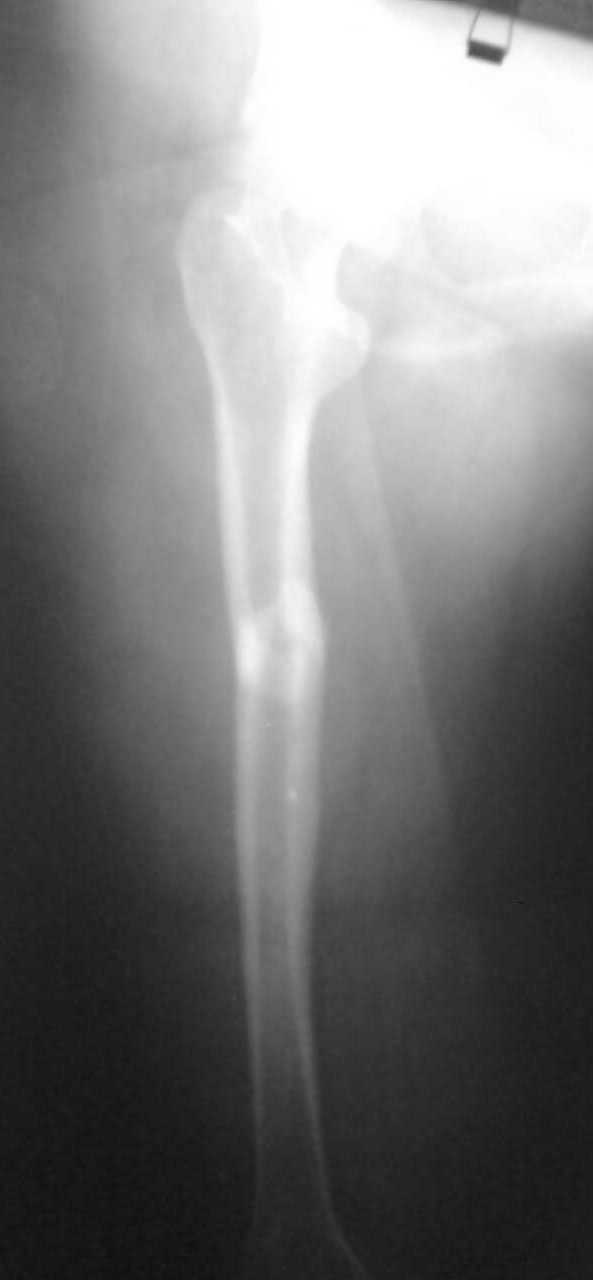

Уважаемый коллега! Не закрадывается ли у вас сомнение, о том не патологический ли это перелом? Учитывая низкоэнергетическую травму, некую реакцию надкостницы и мягих тканей (хотя адекватно оценить трудно - качество и количество;-) снимка). Если - травматический перелом, то я категорично за блокировнный остеосинтез стержнем, особенно в ситуации с человеком с ограниченными способностями.

Немного добавьте подробностей pls - что за перелом? На снимке его толком не видно. Какие имплантаты доступны?

Перелом поперечный с незначительным смещением и с захождением отломков около 2,0см. Перелом типа А 1.

Некачественный снимок, трудно определить состояние шейки, можно было бы сделать прицельную снимок шейки.

А так какие вопросы могут быть в переломе бедра, если перелом закрытый и внезависимо от механизма травмы "золотой стандарт" интрамедуллярный антеградный блокирующий штифт.